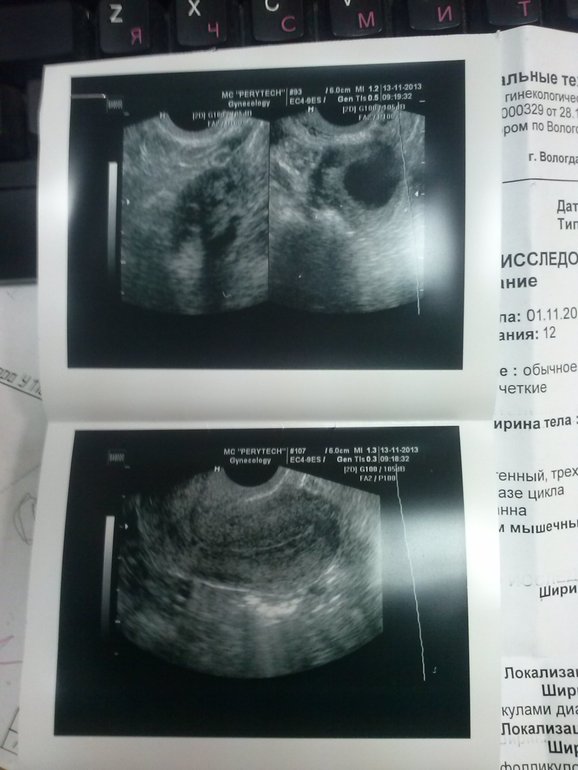

Узи 22 день цикла

Узи 22 день цикла 119 фотографий